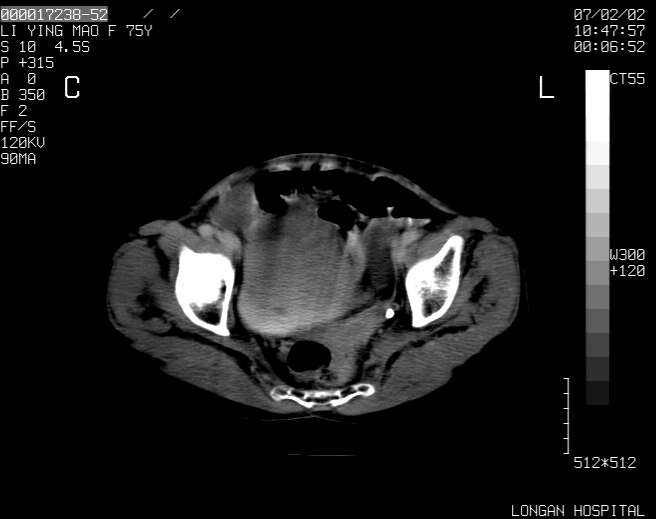

以下是引用dyqct在2007-2-10 8:53:00的发言:[br]考虑:1、肝脏多发囊肿[br] 2、左肾囊肿,右肾多发结石并积水。[br] 3、右胸少量积液。[br] 4、右肾周包裹性积液或淋巴管瘤(有见缝就钻的征象、薄隔、小结节状钙化)?[br] 5、腰椎动脉瘤样骨囊肿?[br] [br] [br]